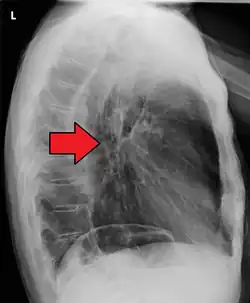

If the cancer has spread elsewhere, symptoms related to metastatic disease may appear. Common sites of spread include nearby lymph nodes, the liver, lungs and bone.[15] Liver metastasis can cause jaundice and abdominal swelling (ascites). Lung metastasis can cause, among other symptoms, impaired breathing due to excess fluid around the lungs (pleural effusion), and dyspnea (the feelings often associated with impaired breathing).

Additional testing is needed to assess how much the cancer has spread (see § Staging, below). Computed tomography (CT) of the chest, abdomen and pelvis can evaluate whether the cancer has spread to adjacent tissues or distant organs (especially liver and lymph nodes). The sensitivity of a CT scan is limited by its ability to detect masses (e.g. enlarged lymph nodes or involved organs) generally larger than 1 cm.[44][45] Positron emission tomography is also used to estimate the extent of the disease and is regarded as more precise than CT alone.[46] PET/MR as a novel modality has shown promising results in preoperative staging with fair feasibility and good correlation in comparison to PET/CT. It can enhance tissue differentiation with lowering the radiation dose to the patient.[47] Esophageal endoscopic ultrasound can provide staging information regarding the level of tumor invasion, and possible spread to regional lymph nodes.